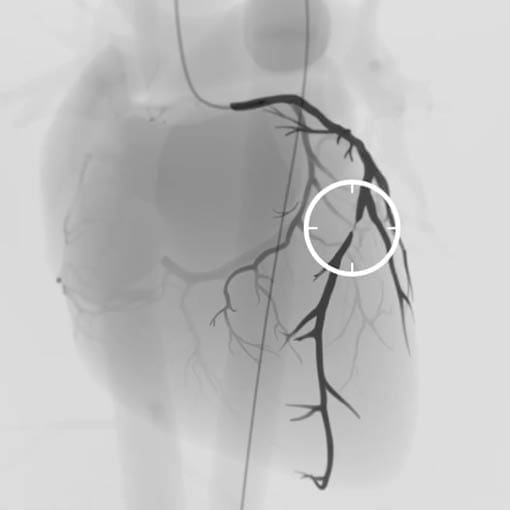

Privatdozent Dr. med. Massimiliano Fusaro ist Facharzt für Innere Medizin und Kardiologie mit den Zusatzqualifikationen der Deutsche Gesellschaft für Kardiologie (DGK) in Interventioneller Kardiologie sowie in der Interventionellen Therapie arterieller Gefäßerkrankungen. Er besitzt die Fachkunde in Röntgendiagnostik und fluoroskopischen Interventionen des Gefäßsystems des Herzens sowie in der Computertomographie des Thorax und des Gefäßsystems bei Erwachsenen und Kindern.

Oberarzt für Interventionelle Kardiologie und Leiter des Programms für komplexe Koronar Interventionen sowie chronische Koronarverschlüsse (CHIP und CTO) am Deutschen Herzzentrum München (Prof. Dr. A. Schömig und Prof. Dr. H. Schunkert)

Ihr Experte für Herzkatheter Therapie - Spezialist für CTO u. periphere Gefäße